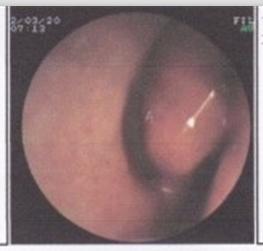

患者病情描述:鼻甲肥大是怎么回事?去了医院里检查了一下说是有下鼻甲或中鼻甲肥大的,想知道鼻甲肥大是怎么形成的?鼻甲肥大如何治疗?

传统手术治疗:鼻甲肥大的治疗基本上采取手术方法,手术的方法有冷冻手术、下鼻甲部分切除术、中鼻甲部分切除术。在治疗上下鼻甲切除不宜过多,原则上不超过下鼻甲的1/3,以免影响鼻粘膜功能或继发萎缩性鼻炎。由于传统的手术治疗疼痛大、出血多、易留疤痕、复发的机率大很多的患者都不愿意接受传统手术治疗。